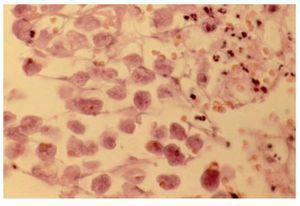

Se realizó biopsia de la lesión exofítica, con el reporte histopatológico de amibiasis cutánea (Figura 3). Se dio tratamiento al paciente con metronidazol 500 mg vía oral cada ocho horas por diez días y baños de asiento tres veces al día con agua tibia, con remisión de los síntomas y de las lesiones a los 15 días.

¿ Figura 3. Microfotografía a gran aumento, hematoxilina y eosina, de trofozoítos de Entamoeba histolytica hematófagos en úlcera cutánea perianal.